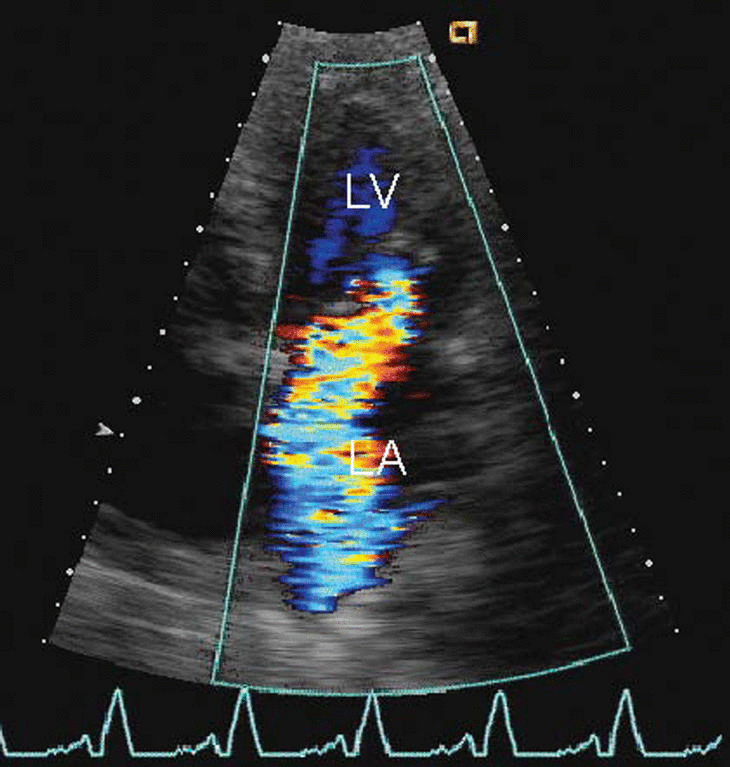

Media attachments